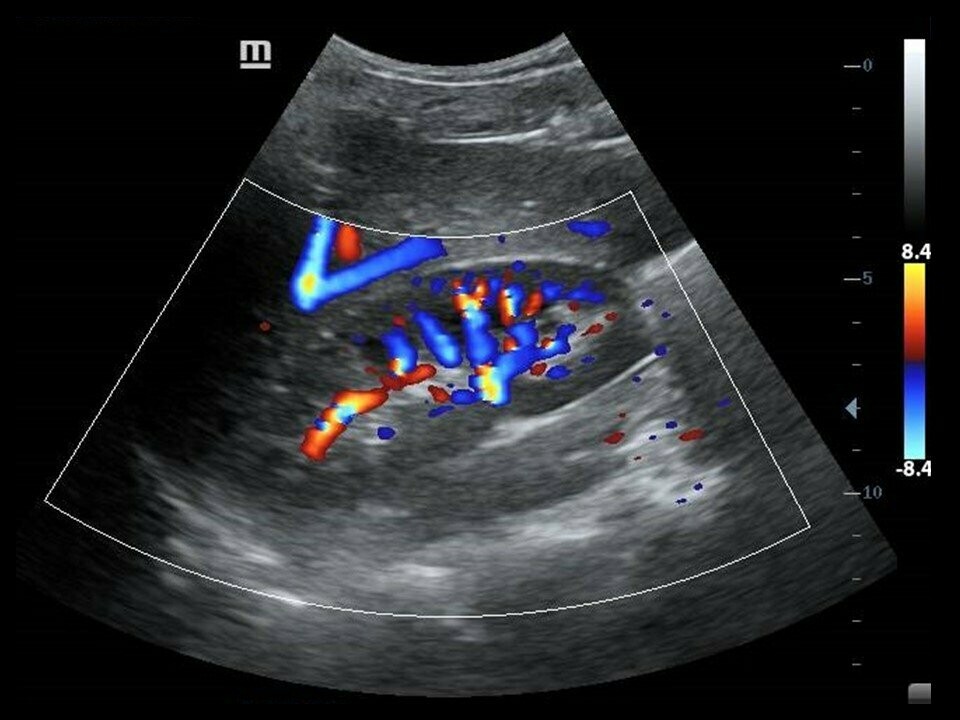

WebUna de las indicaciones principales de la ecografía doppler de arterias renales es el estudio de la estenosis de la arteria renal. Esta patología se asocia a dos síndromes. WebEn la práctica clínica, el doppler se utiliza para evaluar el flujo sanguíneo por medio de la medición del movimiento de los glóbulos rojos, permitiendo obtener información respecto.